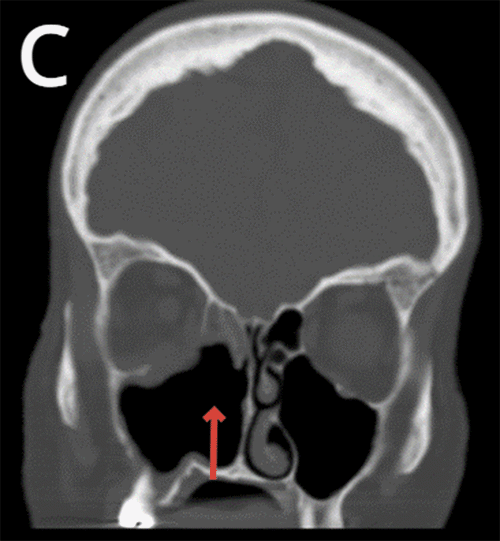

Non-contrast head CT reported the absence of the medial wall of the right maxillary sinus as well as the right inferior nasal turbinate with moderate mucosal thickening within the right frontal, bilateral ethmoid, right sphenoid, and maxillary sinuses indicating chronic sinusitis (Figure 1).

Figure 1. CT Imaging Demonstrating Patient's Extensive Bony Destruction. Published with Permission

A) Arrow pointing at loss of medial wall of right maxillary sinus

Patients with chronic invasive sinusitis with mucormycosis present with non-specific symptoms, including facial pain, facial pressure, headache, mucoid nasal discharge, fevers, nasal congestion, periorbital edema, proptosis, blindness, and cacosmia with the most frequently reported of these being unilateral facial pain.1 Of note, our patient reported several symptoms, including nasal congestion, facial pressure, visual changes, eye drooping, and sinus drainage, for months before presenting to our office. Diagnostic workup includes head CT, MRI, nasal endoscopy, and surgical intervention to retrieve cultures and tissue biopsies for pathologic confirmation. Imaging modalities can reveal the destruction of nasal turbinates, bony erosions, and hyperattenuating allergic mucin. Our patient's diagnostic imaging revealed extensive underlying bony destruction despite having minimal dysmorphic facial features before surgical intervention.